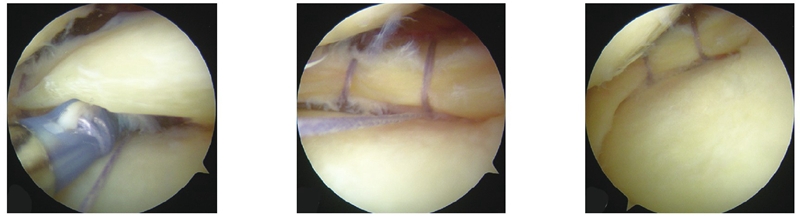

镜下可见外侧半月板体部及后角桶柄样撕裂、前交叉韧带撕裂,使用Omnispan(12°)系统对外侧半月板进行缝合(图3)。半月板处理完毕后,行前交叉韧带重建,最后于股骨内髁处切开并探查内侧副韧带,见内侧副韧带撕裂,直视下锚钉修复内侧副韧带,创面止血后依层次缝合,棉垫弹力绷带包扎伤口,手术完毕。因患者术前有肌间静脉血栓,为避免血栓加重,未使用止血带。

图3 关节镜下手术过程术中照 a 缝合器行垂直褥式缝合;b进行第二针缝合;c 缝合完毕后状态